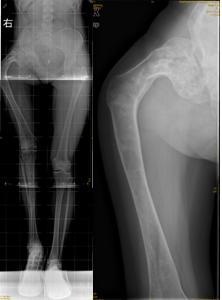

图4 女性,17岁,术前肢体短缩4cm图5 术后2年复查肢体等长,截骨处愈合

图6 女性,21岁,双侧DF 图7 术后5年力线正常,截骨愈合好